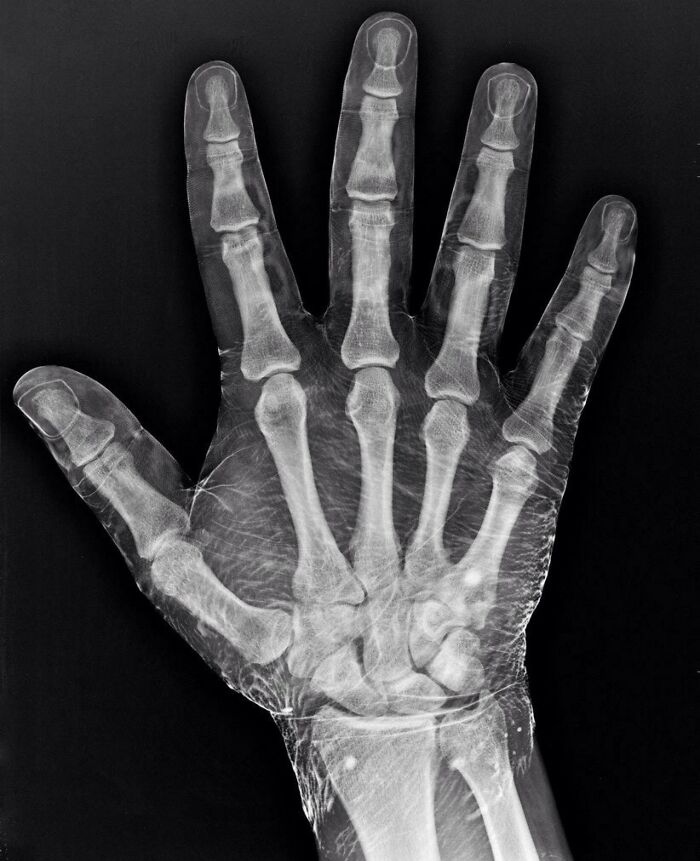

#12 X-Ray Of A Hand Dipped In Iodine. Iodine Absorbs X-Rays, Revealing The Skin Around The Bones